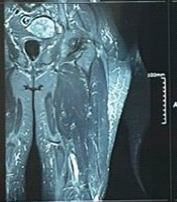

Fungal Infection of Native Hip Joint Presenting as Secondary Arthritis in 52-Year-Old Male – A Rare Case Report

Vikram Venkatesh Raykar , Praveen Mereddy , Shashi Kanth Godey , Veda Prakash G

………………………………p.185-187